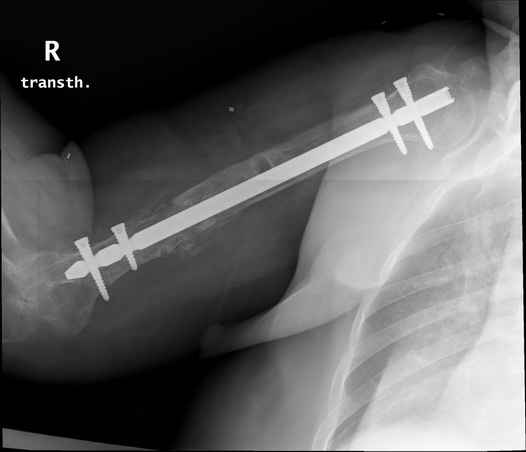

Больная 48 лет, медсестра-массажист, перелом плеча 7 лет назад, оперирована 4-кратно и безуспешно

Больная 48 лет, медсестра. Травма получена 7 лет назад, оперирована первично в Турции - остеосинтез пластиной - несращение - реостеосинтез стержнем там же через год (обычным, с выстоянеием его в полость плеча) - несращение - поступила к нам впервые в марте 2008 года - удаление стержня, реостеосинтез пластиной и костная пластика, в течение 2 лет лизис кости вокруг винтов, смещение фиксатора, в марте 2010 - удаление пластины, реостеосинтез интрамедуллярным стержнем с блокированием (рассверливание + костная пластика). В динамике - вновь лизис в области перелома, нестабильность дистальных блокирующих винтов.

Клинически фиксация пока действительно стабильна, но на рентгенограммах резорбция кости в области дистальных блокирующих винтов и миграция одного из них.